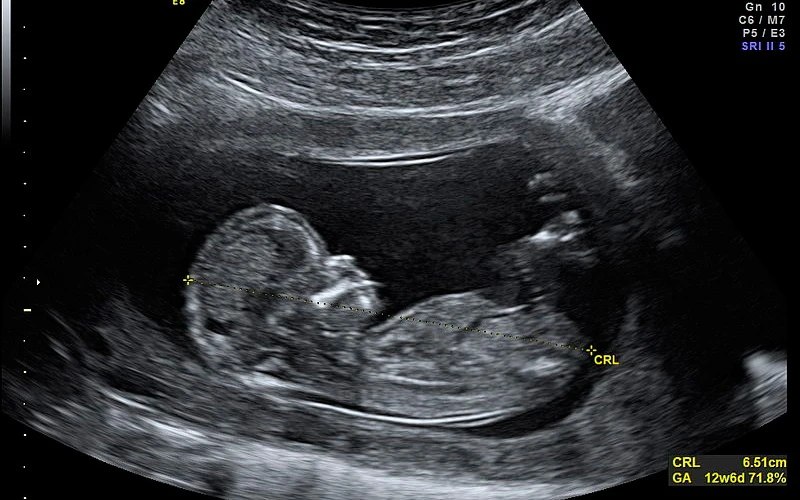

LONDRES, 24 Jul. 14 / 11:07 am (ACI/EWTN Noticias).- El Papa Francisco envió un mensaje con motivo de la Jornada por la Vida que se celebra el 27 de julio en Inglaterra, Irlanda, Escocia y Gales, para pedir “la protección jurídica adecuada para el derecho humano fundamental a la vida” y combatir la cultura de muerte.

El lema de la Jornada por la Vida 2014 es “#livelife Proteger y apreciar la vida desde su comienzo hasta su final natural” y constituye una invitación a los jóvenes, sobre todo, a participar del cuidado, la crianza y la protección de la vida en cada etapa y en cada condición.

La Jornada por la Vida se celebra anualmente por la Iglesia Católica en Escocia, Inglaterra, Gales e Irlanda, y está dedicada a crear conciencia sobre el significado y el valor de la vida humana en cada etapa y en cada condición.

Esa iniciativa legislativa popular, titulada también “One of Us”, recordaron, “que ahora ha tomado la recién formada Federación, pedía el respeto a la vida humana en todos los ámbitos en los que la Unión Europea tiene competencias y que no se emplearan fondos públicos para actividades que la destruyeran o atacaran su dignidad”.

Su segundo objetivo, apuntaron, es el de buscar “el desarrollo de una Cultura de la Vida en Europa, a través de la promoción de y el apoyo a actividades que impliquen la protección de la vida humana, particularmente en sus estadios más vulnerables de desarrollo (concepción y gestación, infancia, maternidad, enfermedad, ancianidad y final de la vida)”.